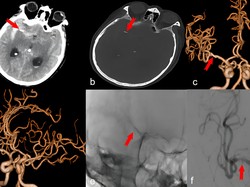

Pasutri Wajib Waspada! Dokter Bicara Risiko Sakit Kepala-Stroke Usai Bercinta

Pasutri wajib mewaspadai sakit kepala yang dapat muncul ketika berhubungan seks. Dokter juga mengingatkan risiko stroke yang mungkin terjadi setelah bercinta.